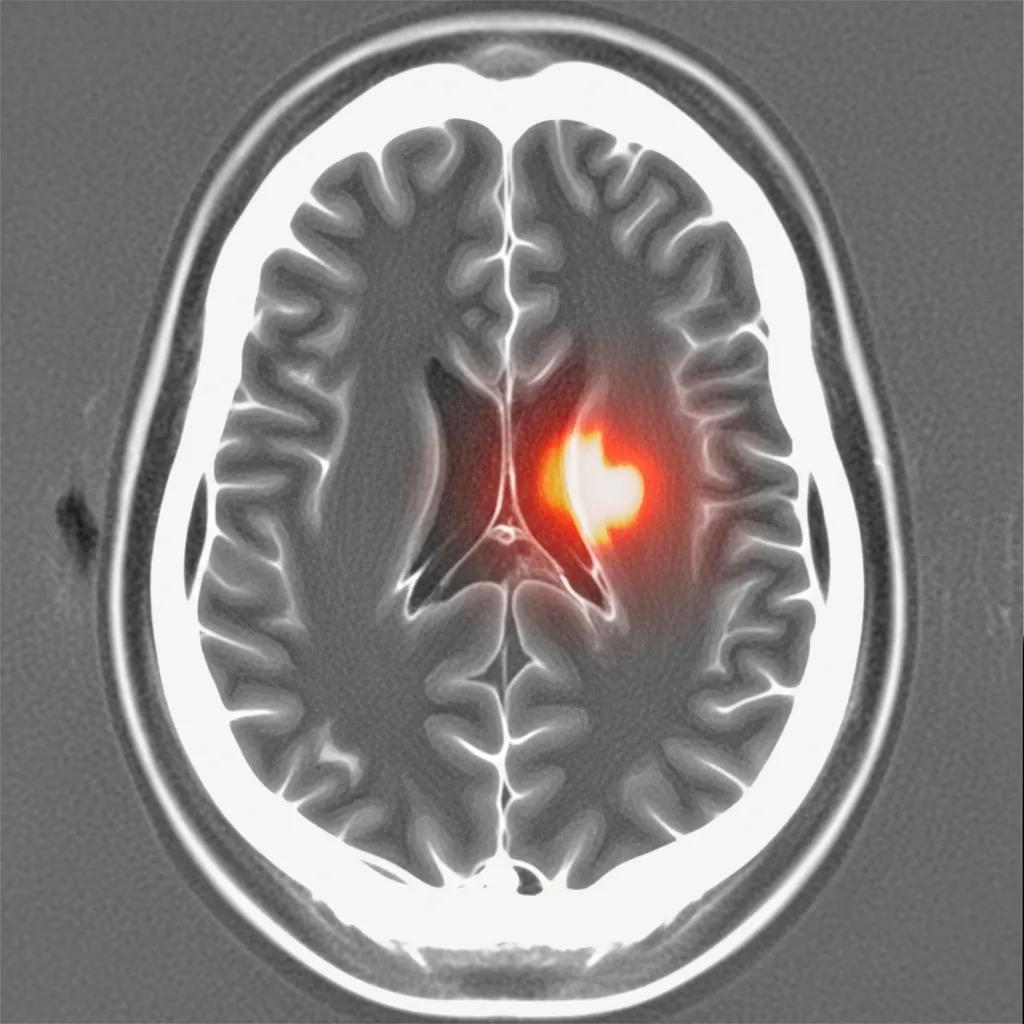

- Stroke: CT scans can quickly reveal the presence of a stroke, allowing for timely intervention.

- Brain Tumors: These scans help in detecting tumors, assessing their size, and determining their location.

- Hemorrhages: A brain CT scan can identify bleeding within the brain, which is crucial for emergency treatment.

The ability to diagnose these conditions promptly is vital, as it can significantly impact treatment outcomes and patient recovery.

Brain CT scans utilize advanced imaging technology to detect strokes and hemorrhages. The process involves taking multiple X-ray images from different angles, which are then processed to create detailed cross-sectional images of the brain.

When a stroke occurs, either due to a blockage (ischemic stroke) or bleeding (hemorrhagic stroke), the CT scan can show changes in brain tissue and blood flow. Rapid imaging is essential, as it allows healthcare providers to determine the type of stroke and initiate appropriate treatment quickly. You can find more information about brain CT scans on specialized radiology websites.